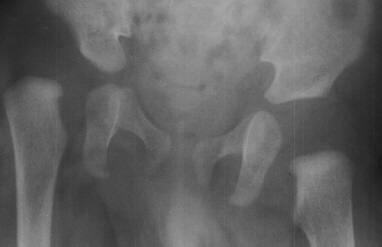

This 29 week gestation male was born by vaginal delivery. These x-rays were made after it was noted that that the knees appeared to be hyper-extended. The right knee had -30 degrees extension to 20 degrees of flexion. The left knee had -20 degrees extension to 20 degrees of flexion. Ortolani exam revealed a positive sign in the left hip and a negative sign in the right. Knee splints were applied. In two weeks the knees were able to flex to 75 degrees bilaterally.